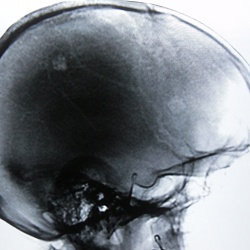

Военнослужащий 44 лет, поступил в хирургическое отделение госпиталя с мочекаменной болезнью. Попутно по поводу головных болей выполнена цифровая флюорография черепа - и понеслось. В моче кроме...